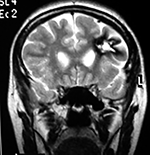

Paciente masculino de 34 años de edad, quien presenta crisis convulsivas parciales motoras de brazo y hemicara derecha, secundariamente generalizadas, posteriormente hemiparesia 4/5 para hemicuerpo derecho.

La TAC muestra un área hiperdensa a nivel frontal izquierdo heterogénea que no refuerza con medio de contraste.

LA RMN muestra una lesión bien circunscrita frontal parasagital izquierda con edema perilesional, hiperintensa en T1 y T2, de contenido sólido y quístico, con poca captación del medio de contraste.

Se realizó craneotomía frontal para abordaje interhemisférico anterior.

Se realiza resección total de la lesión de contenido hemático oscuro-verdoso, consistente en un angioma cavernoso. La RMN postoperatoria se observa solo la brecha quirúrgica sin evidencia de lesión.

En el postquirúrgico el paciente desarrollo síndrome frontal lateral, que se controló con Risperidona y remitió después de tres semanas, las crisis convulsivas remitieron y el medicamento se disminuyó de manera paulatina (figs. 4 y 5).

Figura 4:

Imágenes prequirúrgicas y postquirúrgicas de lesión multiloculada del caso 9.